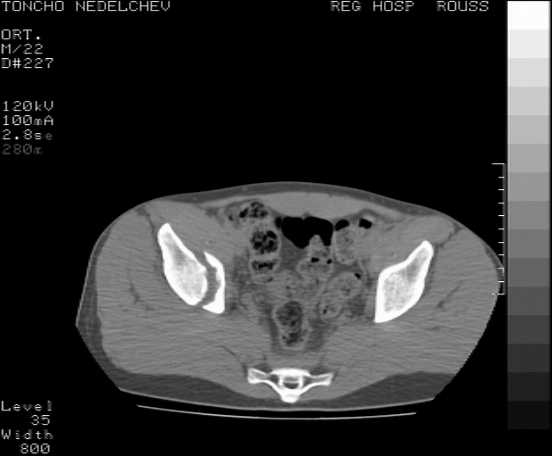

Here are some more axial images. What is your opinion as for the timing of the operative treatment?